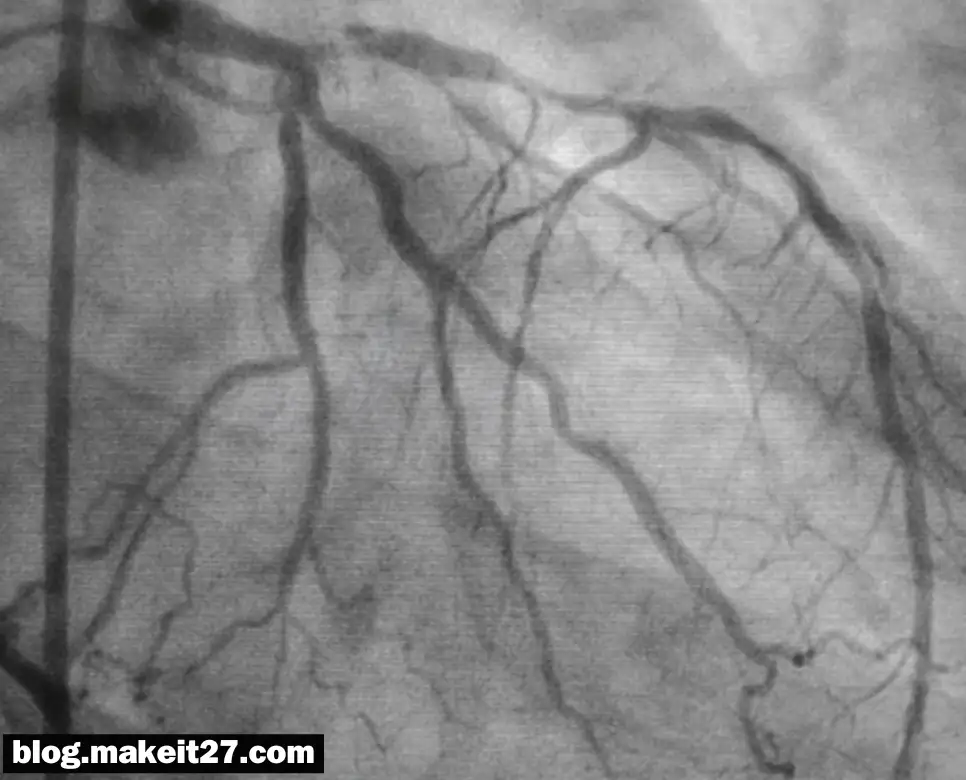

CAG는 ‘Coronary Angiography’의 약자로, 한국어로는 관상동맥조영술이라고 합니다. 이 검사는 심장을 공급하는 혈관인 관상동맥의 협착, 폐쇄, 확장, 연축, 혈전 등을 확인하기 위해 시행됩니다. 주로 심장카테터 검사의 일부로, 요골동맥(radial artery)이나 대퇴동맥(femoral artery)을 통해 카테터를 삽입하고, 관상동맥 입구에 위치시켜 조영제를 주입하여 혈관의 상태를 관찰합니다.

이러한 검사와 시술은 협심증이나 심근경색과 같은 관상동맥 질환의 진단과 치료에 중요한 역할을 합니다. 검사를 통해 관상동맥의 상태를 정확히 파악하고, 필요한 경우 스텐트 삽입과 같은 중재술을 통해 혈관을 넓히거나 뚫어 혈류를 개선할 수 있습니다. 이는 개흉술을 하지 않고도 심장의 혈관 상태를 개선할 수 있는 중요한 방법입니다.